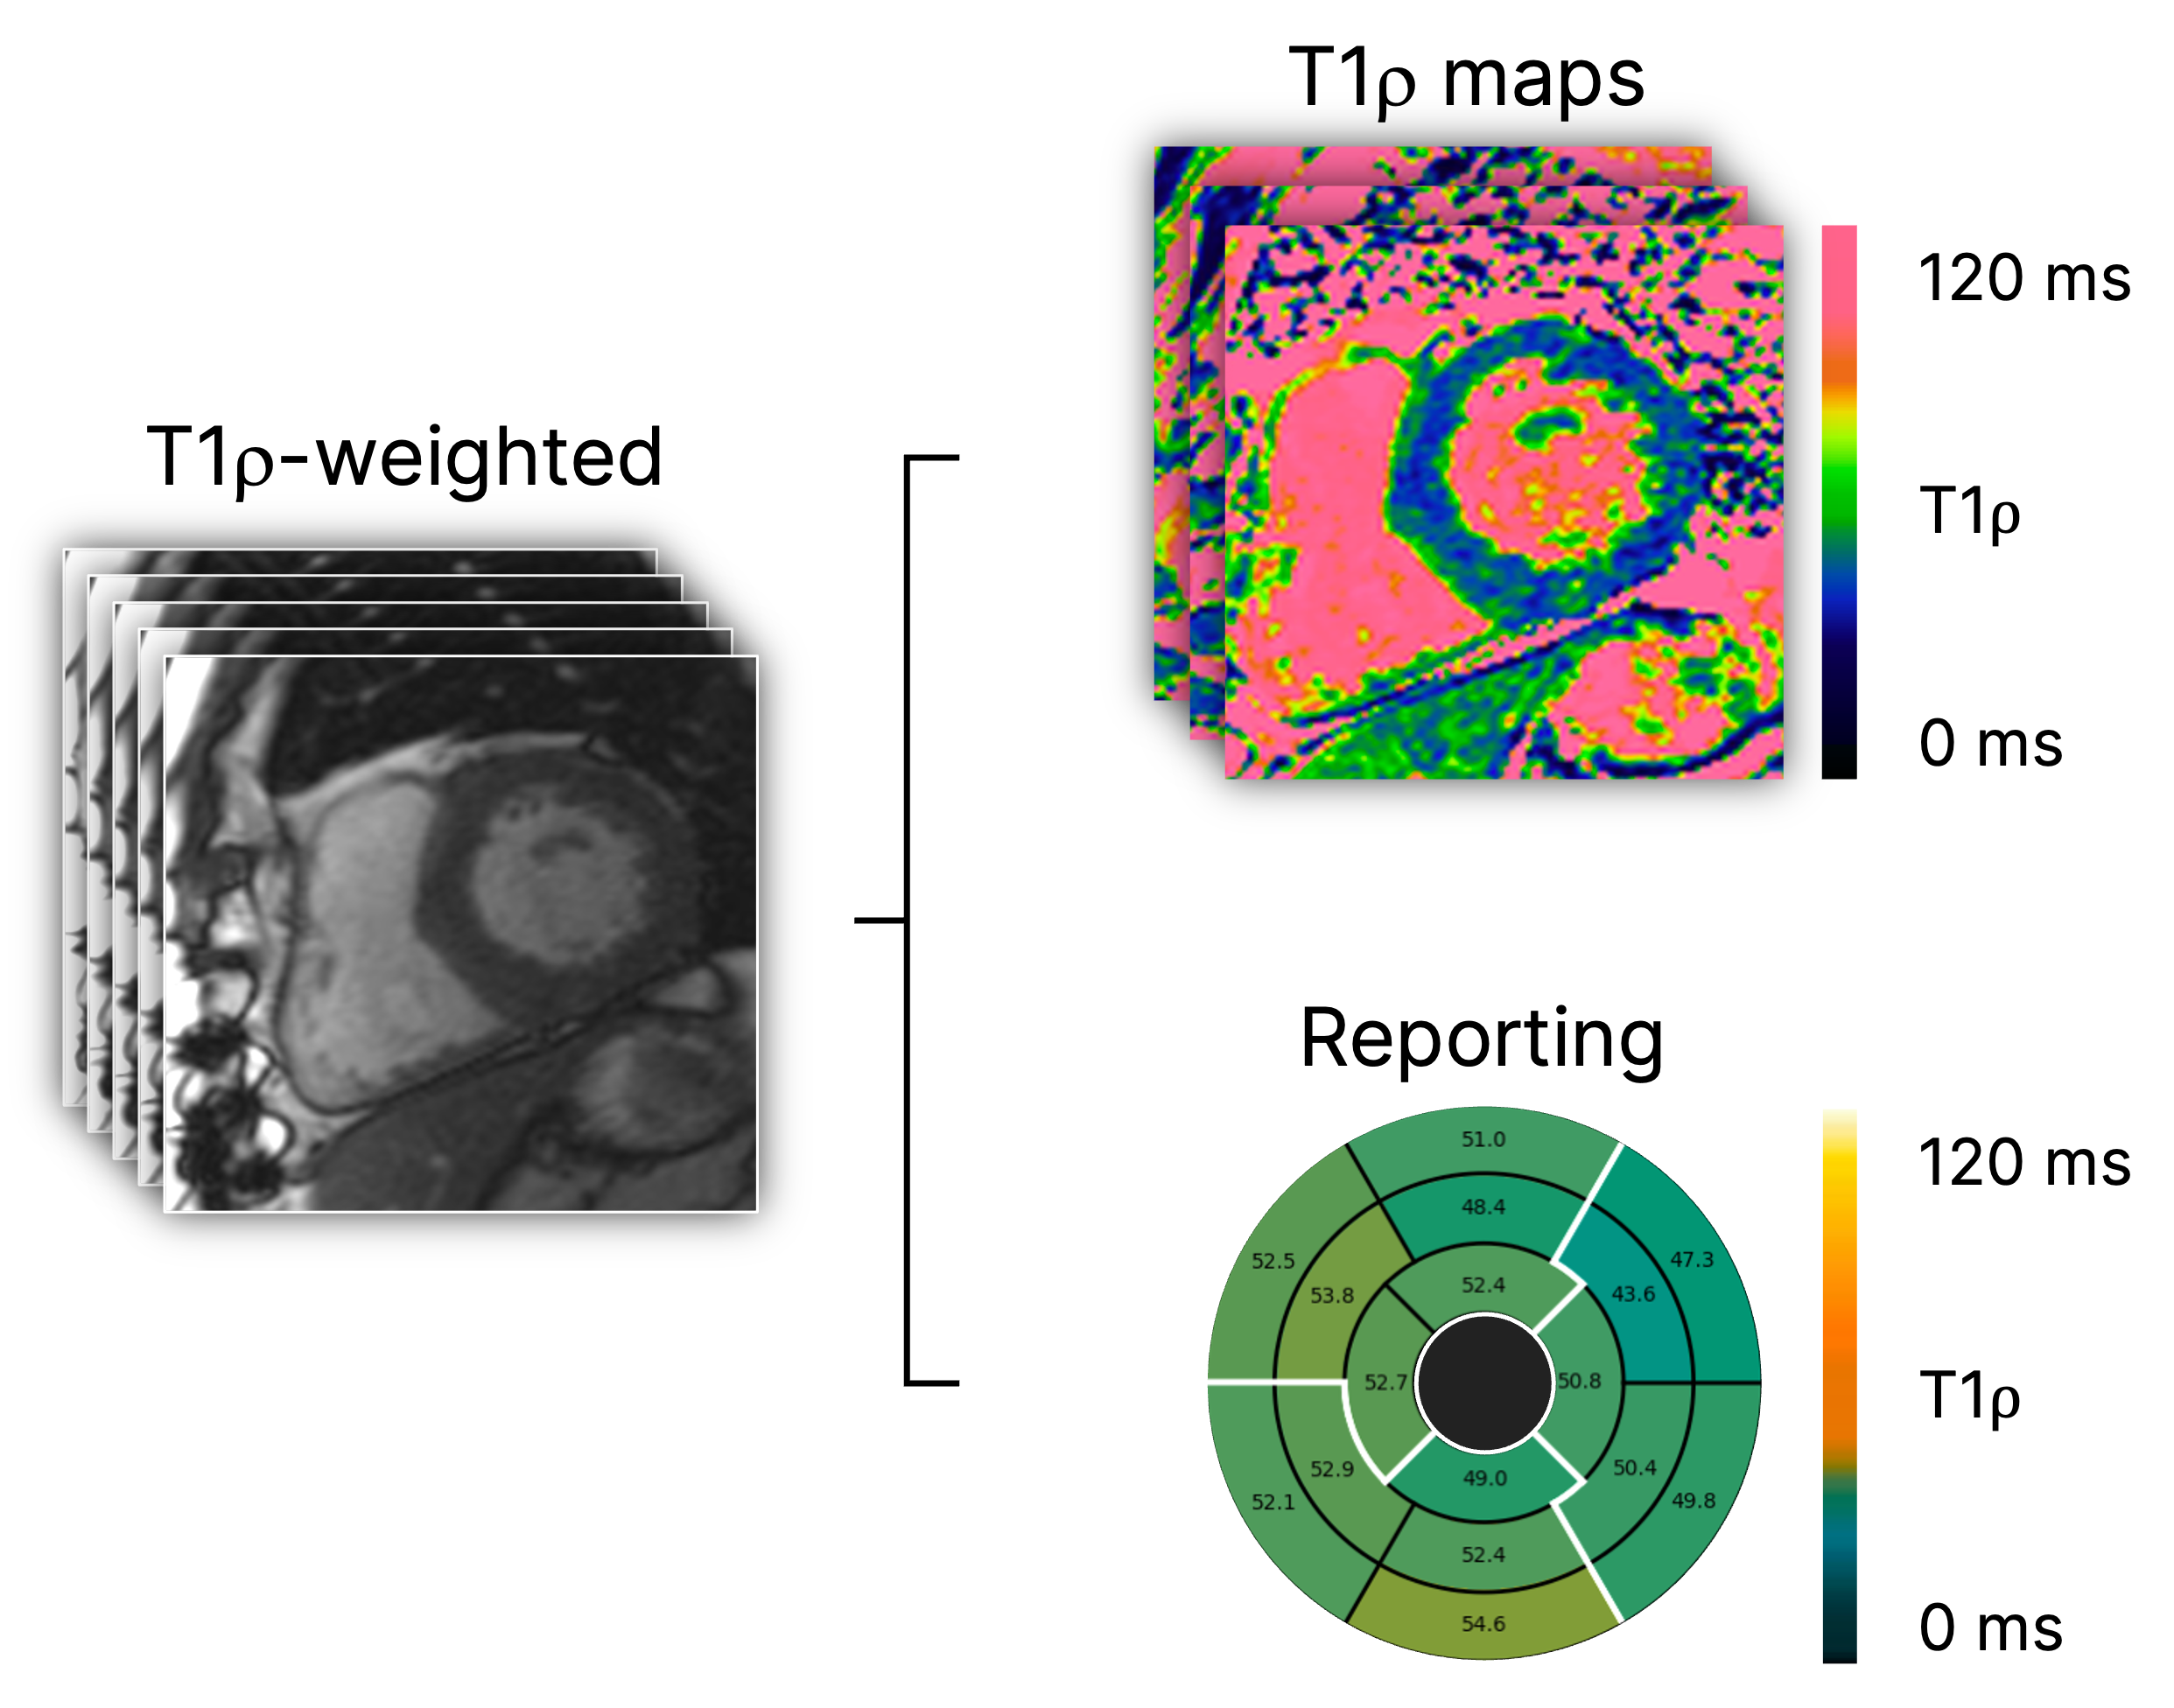

T1-rho mapping

Contrast agent-free myocardial scar characterization